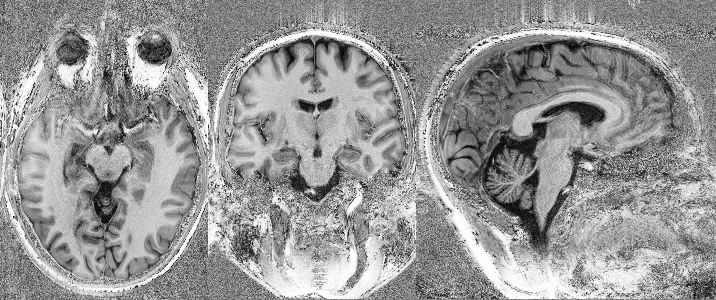

Commissioning of the Iseult CEA 11.7 T whole-body MRI: current status, gradient–magnet interaction tests and first imaging experience

Magn Reson Mater Phy. 2023 doi: 10.1007/s10334-023-01063-5.

Progress Toward Medical Use of the Iseult Whole Body 11.7 T MRI: First Images

IEEE Transactions on Applied Superconductivity. 2023. doi: 10.1109/TASC.2023.3244117.

Progress On The Commissioning Of The Iseult 11.7T Whole-Body MRI: First Images

Proceedings of the ISMRM 2022, London, UK, p0382.